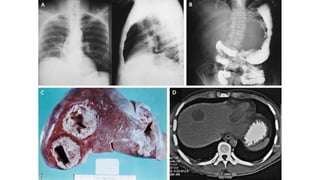

Macroscopic

characteristics of

fulminant amebic

colitis: (a) External

view of the colon, where

large areas of

hemorrhagic necrosis

(*) and perforations can

be appreciated

(arrows); small normal-

looking areas of the

colon and the

mesentery (**)

Amebic liver abscess

 In about 5-10% of persons with intestinal amebiasis.

 The center of the abscess contains thick chocolate brown pus (anchovy

sauce pus), which is liquefied necrotic liver tissue.

 Its bacteriologically sterile and free of ameba.

 At the periphery almost normal liver tissue contains invading ameba.

 Liver abscess may be multiple or more often solitary,

 Located in the upper right lobe of the liver.

 Cardinal sign painful hepatomegaly.

Macroscopic characteristics of fulminant amebic colitis:(a) External view of the colon, where large areas of hemorrhagic necrosis (*) and perforations can be appreciated (arrows); small normal- looking areas of the colon and the mesentery (**)

E. histolytica Clinical Features Amebicliver abscess  In about 5-10% of persons with intestinal amebiasis.  The center of the abscess contains thick chocolate brown pus (anchovy sauce pus), which is liquefied necrotic liver tissue.  Its bacteriologically sterile and free of ameba.  At the periphery almost normal liver tissue contains invading ameba.  Liver abscess may be multiple or more often solitary,  Located in the upper right lobe of the liver.  Cardinal sign painful hepatomegaly.